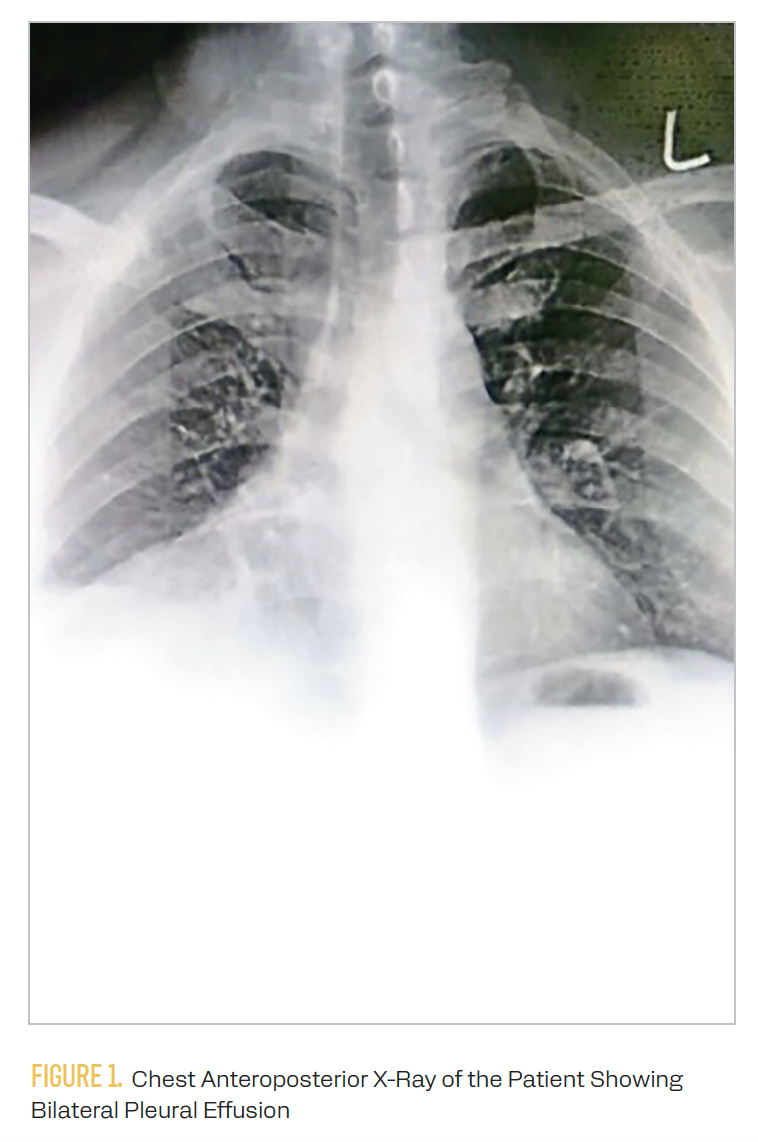

Table 12-4 indicates the laboratory findings of the patient. A chest x-ray confirmed pulmonary effusion, as shown in Figure 1.

FIGURE 1. Chest Anteroposterior X-Ray of the Patient Showing Bilateral Pleural Effusion